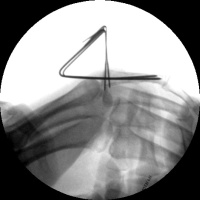

Case 1.

A malaligned three

week old fracture. Notice the

typical zig zag collapse pattern resulting in flexion

of the proximal interphalangeal

joint to the same degree as the fracture angulation. |

| Intraoperative

fluoroscopy. |